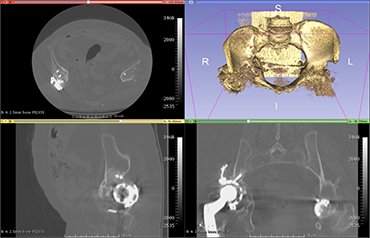

Once the patient’s CT (Computed Tomography) scan or MRI (Magnetic Resonance Imaging) films are sent to us, our engineers convert these images into 3D.

Step 1: The patient’s MRI film is converted into 3D.